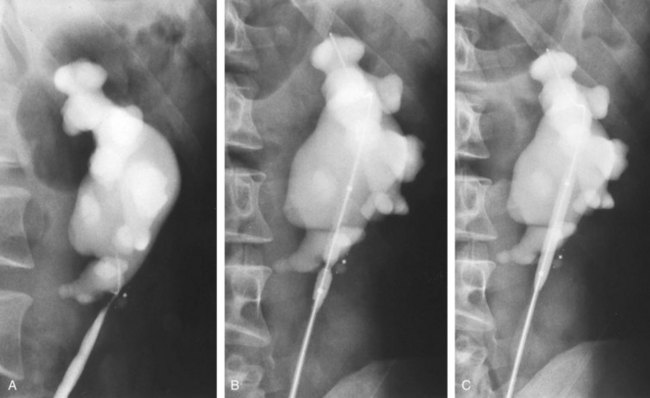

In the original descriptions of the technique both from the Institute of Urology in London (Ramsay et al, 1984) and from Long Island Jewish Hospital in New York (Badlani et al, 1986), the endopyelotomy was performed using a cold knife technique under direct vision. With one or two wires in place across the UPJ, a direct vision “endopyelotome” is used. This hook-shaped cold knife may be used to completely incise the UPJ in a full-thickness manner, from the ureteral lumen to periureteral and peripelvic fat (Fig. 41–8). Rigorous anatomic studies have shown the incision should generally be made laterally because this is the location devoid of crossing vessels (Sampaio, 1998). However, in cases of high insertion, the incision should instead “marsupialize” the proximal ureter into the renal pelvis, such that an anterior or posterior incision may be required (Fig. 41–9). When such incisions are done under direct vision, any crossing vessel can be directly visualized and avoided. In addition to the endopyelotome, the holmium laser or the cutting balloon catheter may also be used to perform an antegrade endopyelotomy.

Figure 41–8 Percutaneous nephroscopic view of “cold knife” endopyelotomy (inset). The line of incision is delineated by two guidewires, which have been passed across the ureteropelvic junction in an antegrade fashion through a superior calyx using a rigid nephroscope through a 30-Fr sheath. The lateral incision is performed under direct visual control.

Figure 41–9 A, Retrograde study in this patient with left ureteropelvic junction obstruction reveals a “high insertion” of the left ureter. B, CT scan in this same patient reveals the ureter inserting on the anatomically anterior aspect of the renal pelvis. A marsupializing incision must be made in a true posterior direction from the ureter into the renal pelvis.